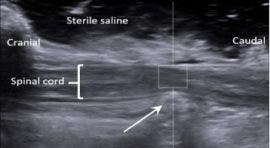

In connection with this research, the neurology team at Highcroft is undertaking another research project (led by Drs Jon Prager and Nicolas Granger) with the objective to measure swelling of the spinal cord during surgery. This is possible using the ultrasound machine at Highcroft Veterinary referrals, which is equipped with specific software that can measure how quickly sound waves propagate within tissue, a technique called ‘elastography’. In essence, ultrasound elastography gives a reading of the ‘stiffness’ or ‘elasticity’ of tissue. Due to the delicate nature of the spinal cord, it is suggested that its structure, and therefore its elasticity, changes after injury. In a set of preliminary data we have collected, it appears that how much the spinal cord elasticity changes after injury is related to the clinical severity of injury, and we are proposing to continue to describe these changes. In time, this novel measure may allow more accurate prognosis for dogs that have spinal cord injury.